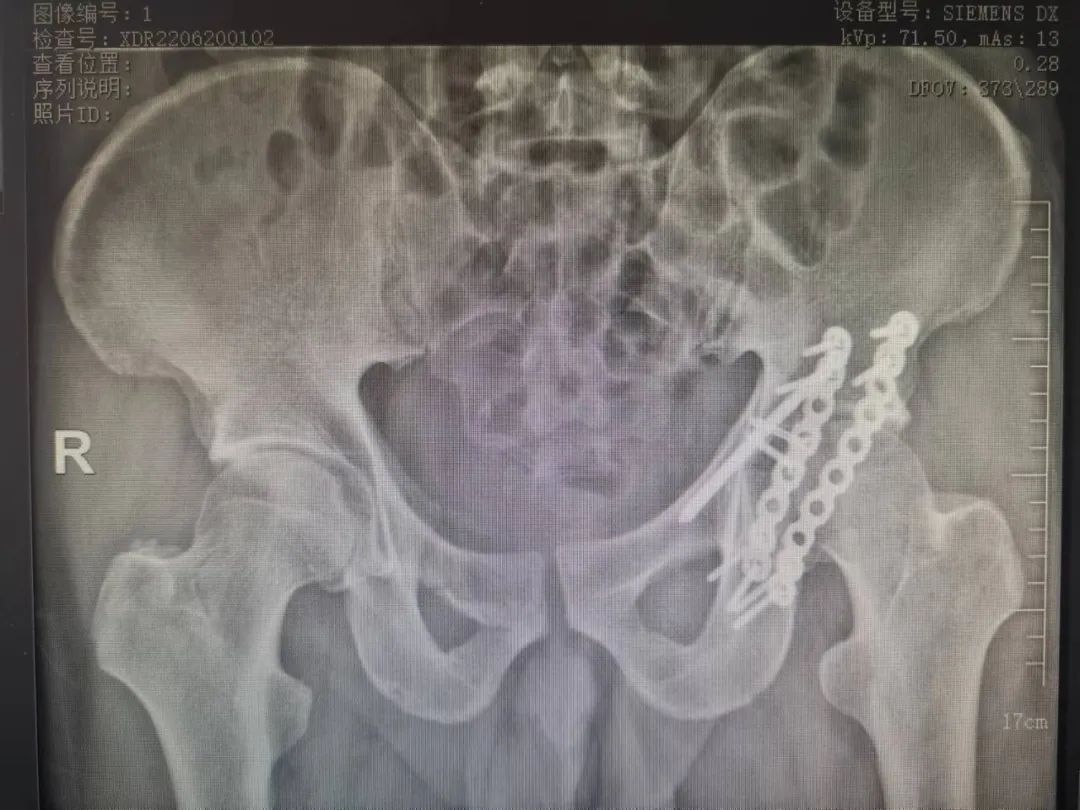

张洪彬医生对患者骨盆三维CT进行了术前虚拟仿真,辅助术者规划骨折复位过程及通道螺钉的置入长度、角度及方向。在患者伤后2周内,由刘利主任主刀,采取单一Kocher-Langenbeck 入路手术入路,术中仔细对坐骨神经及旋股内侧动脉进行了保护,降低了远期发生神经损伤及股骨头缺血性坏死发生风险,完成复位后,应用两块重建钢板及一枚通道螺钉就完成了复杂骨折的固定。术后复查DR及CT骨折复位理想,内固定位置满意,没有发生螺钉进入关节腔的情况。患者得到了早期功能康复锻炼的有利条件。患者现已顺利出院。